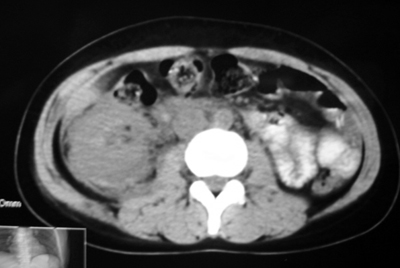

以下是引用bmw011在2009-4-23 13:28:00的发言:[br]考虑右肾包膜下血肿。

以下是引用卜一在2009-4-23 15:43:00的发言:[br]考虑右肾包膜下血肿,不排除占位病变伴出血可能,建议进一步检查。